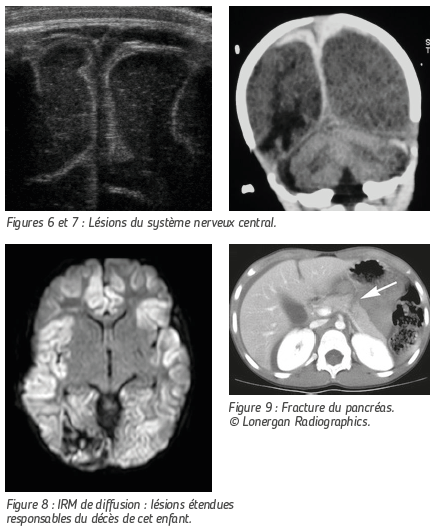

Ici encore, le mécanisme lésionnel le plus fréquent chez le nourrisson est le secouage. L’enfant ainsi maltraité peut alors souffrir de graves lésions cérébrales dont les séquelles seront responsables de handicap et qui peuvent entraîner la mort de l’enfant.

L’échographie transfontanellaire n’est pas formellement indiquée mais dans certaines circonstances, elle permet de mettre en évidence fortuitement et de façon non irradiante les lésions hémorragiques interhémisphériques « biphasiques » typiques.

Le CT Scanner est d’accès facile et permettra lui aussi de mettre en évidence les zones de contusion, les hématomes et les ruptures des « veines ponts ».

L’IRM est indispensable pour le bilan lésionnel complet. Cet examen n’est pas pratiqué en urgence car il nécessite une anesthésie générale chez le petit enfant.

Les séquences adaptées permettent d’évaluer l’étendue des lésions anoxo-ischémiques dont le pronostic peut être très sombre en matière de séquelles, voire de survie de l’enfant.

L’enfant maltraité peut être aussi victime de lésions viscérales : fracture du pancréas, du foie ou de la rate. L’échographie et le scanner permettent d’en faire le diagnostic.